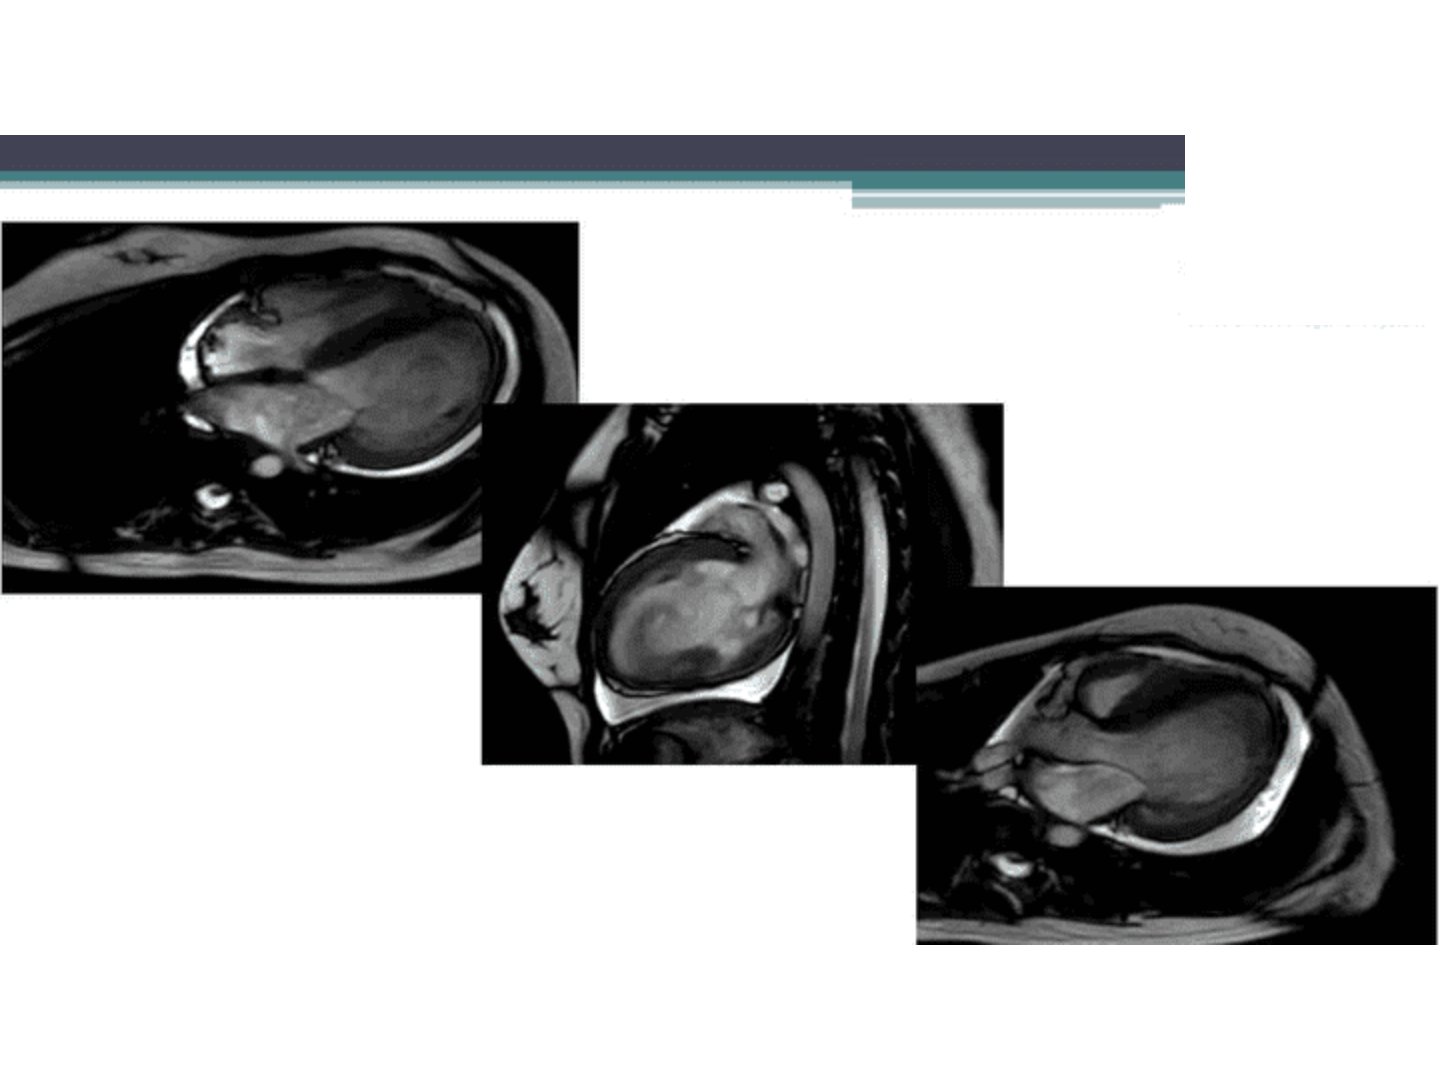

如何看懂心脏磁共振报告心脏磁共振报告包含多方面关键信息帮助医生全面了解心脏状况。首先是心脏结构部分会描述心脏各腔室大小如左心室、右心室、左心房、右心房若腔室扩大可能提示特定疾病。还会提及心室壁厚度异常增厚或变薄都可能是疾病信号。接着看心肌情况报告会说明心肌有无水肿、坏死或纤维化。水肿可能见于心肌炎坏死多与心肌梗死相关纤维化则可能提示慢性心肌病变。心脏功能方面会评估心脏收缩和舒张功能常用射血分数等指标数值异常反映心脏泵血功能好坏。此外报告可能提及心脏血管情况有无血管狭窄、畸形等。最后报告会给出诊断建议如是否存在心肌病、先天性心脏病等为后续治疗提供重要依据。患者若对报告有疑问应及时与医生沟通。